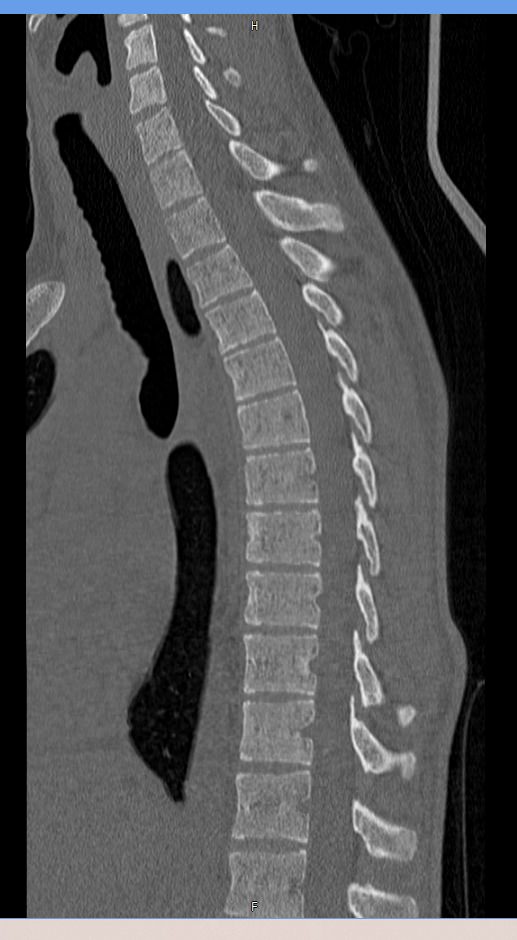

Мультиспиральная компьютерная томография – это современный быстрый и точный способ диагностики заболеваний позвоночника, основанный на использовании рентгеновского излучения. Метод позволяет получать послойные изображения грудного сегмента позвоночного столба, включая 12 грудных позвонков, задние отрезки ребер, межпозвоночные диски, позвоночный канал.

При помощи инновационных компьютерных программ данные преобразуются в трехмерные изображения позвоночного столба с сосудами, нервами и лимфатическими узлами в мельчайших подробностях. Наглядные объемные 3D-изображения высокого качества помогают в диагностике различных заболеваний позвоночника и бывают особенно полезны при планировании хирургических операций, при оценке эффективности проведенного лечения.

Что показывает компьютерная томография грудного отдела позвоночника

- изменения структуры и расположения позвонков и окружающего их мышечно-связочного аппарата

- аномалии развития позвоночника

- травмы позвоночного столба (переломы и трещины)

- ширину спинномозгового канала

- признаки наличия межпозвоночной грыжи (протрузии, экструзии)

- абсцессы, туберкулёзное поражение, новообразования, наличие метастазов и прорастание опухолей из соседних органов

- изменения в спинном мозге (кровоизлияния и др.)

- дегенеративные изменения

- участки пониженной плотности кости — остеопороз при визуальной оценке